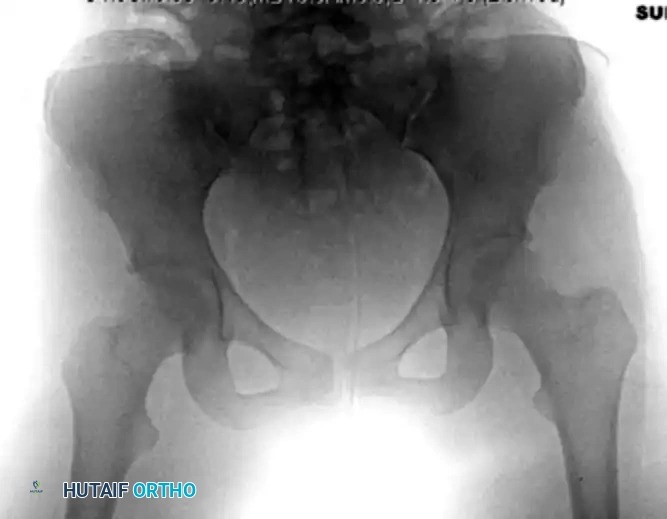

Patients with a pure posterior hip dislocation present with a highly characteristic lower extremity posture. Because the femoral head is displaced posterior and superior to the acetabulum, the limb is typically shortened, adducted, and internally rotated. The hip is usually held in a flexed position.

FIGURE 55-52 A: Characteristic extremity posture of a posterior hip dislocation demonstrating flexion, adduction, and internal rotation.